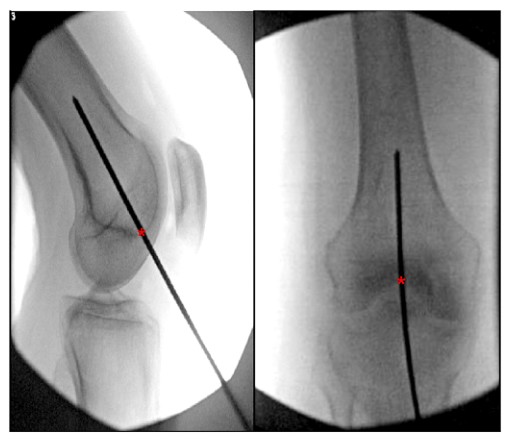

В литературе можно найти множество описаний оптимальной точки входа для ретроградного интрамедуллярного стержня бедренной кости. Большинство исследований определяют идеальную точку входа ретроградного бедренного стержня на расстоянии 1,2 кпереди от бедренного начала задней крестообразной связки.

см (на уровне костномозговой полости) и центра межмыщелковой ямки (рис. 6).

РИСУНОК 6. Интраоперационный ортостатический и боковой вид коленного сустава, показывающий идеальную точку входа для ретроградного бедренного интрамедуллярного стержня. «*» указывает начальную точку интрамедуллярного стержня.